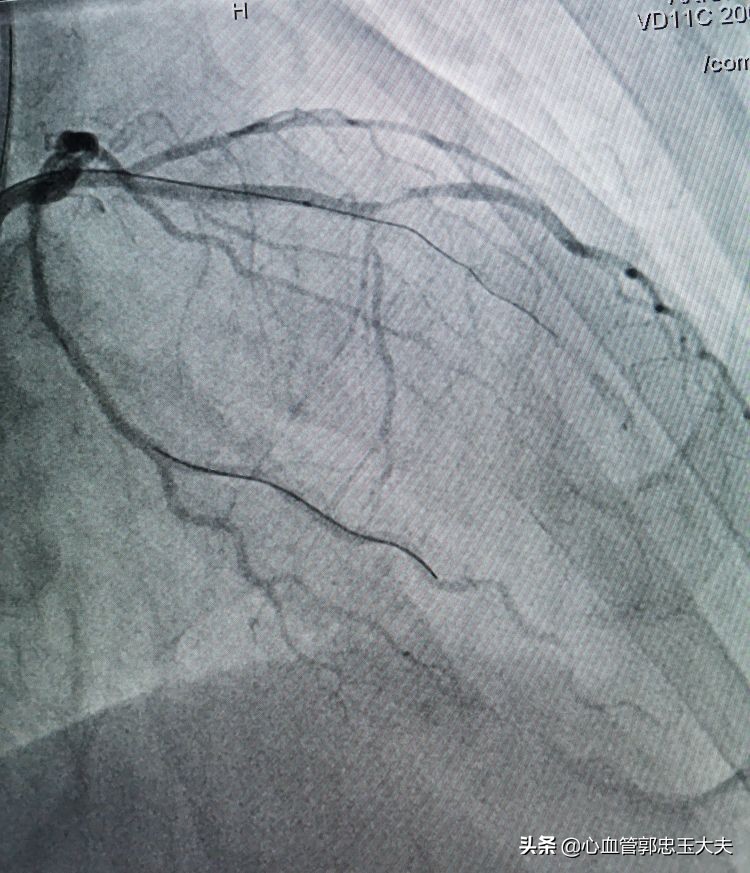

张大爷86岁了,有高血压病史,无烟酒嗜好。因为“反复胸闷头晕数月”入院。冠状动脉CTA示:三支病变,严重钙化合并高度狭窄。行冠脉造影示:前降支中远段钙化,完全闭塞,远端可见血管影。未见明显侧枝循环。(如下图)